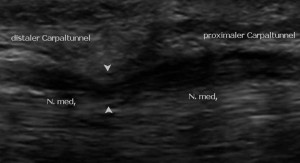

Da die neurologische Untersuchung, insbesondere zu Beginn der Beschwerden häufig keine auffälligen Befunde liefert, wird die Diagnose in der Regel mittels Messung der elektrischen Leitfunktion des Nervens gestellt. Durch die Entwicklung hochauflösender Ultraschallgeräte ist es heutzutage jedoch möglich eine sehr gute und verlässliche Darstellung von Nerven zu ermöglichen, so dass diese Methode nun auch in der Diagnostik des Karpaltunnel-Syndroms eingesetzt werden kann.

Die Ultraschalluntersuchung kann die Kompression und die dadurch hervorgerufene Schwellung des Nervens vor dem Engpass nachweisen und hat eine gleichwertige Aussagekraft und Zuverlässigkeit wie die elektrische Nervenmessung erreicht. Die Kombination beider Methoden erhöht die Treffsicherheit der korrekten Diagnose noch einmal, insbesondere bei leichten Befunden und nach vorherigen Operationen am Karpaltunnel. Ein weiterer Vorteil ist die Darstellung von Lagevarianten von Nerven, Sehnen, Muskeln und Gefäßen oder besonderen Strukturen im Karpaltunnel, so dass der Handchirurg optimierte Information vor einer evtl. notwendigen Operation erhält.